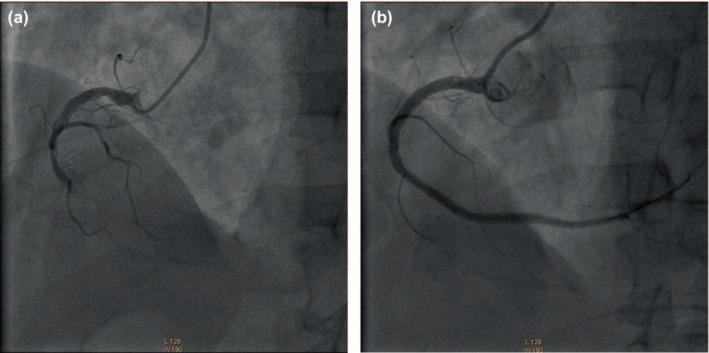

Ivabradine reduces the heart rate by selectively inhibiting the I current of the sinoatrial node, mainly for the treatment of chronic heart failure with decreased left ventricular systolic function and inappropriate sinus tachycardia, but the inhibitory effect on the atrioventricular node is rarely reported. The patient was admitted to hospital mainly because of intermittent chest pain for 7 years, which worsened for 10 days. Admission electrocardiogram (ECG) considered sinus tachycardia, with QS wave and T wave inversion in II, III, aVF, V R-V R, V -V leads, and non-paroxysmal junctional tachycardia (NPJT) with interference atrioventricular dissociation. After treatment with ivabradine the ECG returned to normal conduction sequence. NPJT with interference atrioventricular dissociation is a fairly rare electrocardiographic phenomenon. This case reports for the first time that ivabradine is used in the treatment of NPJT with interference atrioventricular dissociation. It is speculated that ivabradine has a potential inhibitory effect on the atrioventricular node.